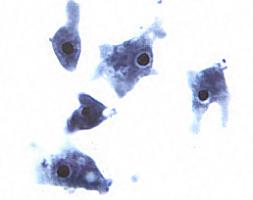

| Taxonomy: | Eukaryota | Heterolobosea | Schizopyrenida | Vahlkampfiidae | Naegleria |

| Comment: | Naegleria is an ameba commonly found in the environment, in water and soil. Only one species of Naegleria has bee found to infect humans, Naegleria fowleri. |